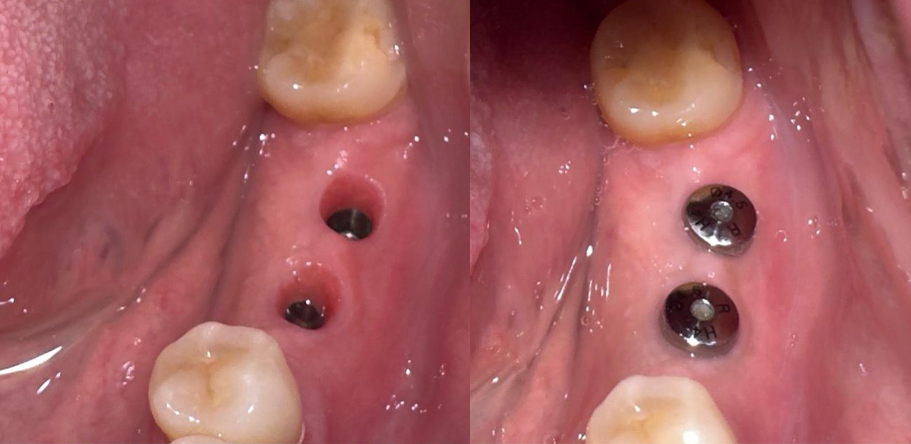

Antes

Después